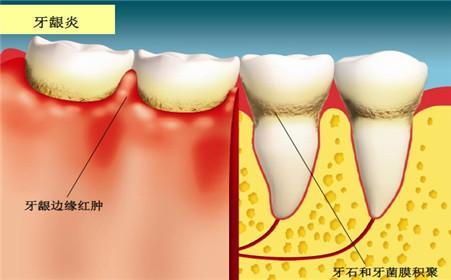

1、导致牙龈出血:牙龈炎

许多人吃辛辣刺激的食物,隔天早上刷牙发现牙龈肿胀,一旦刷牙就牙龈出血,其实就是上火引起的,本来已经是体内火气过盛,导致牙龈发炎,牙龈表皮比较脆弱,这时刷牙会造成二次伤害,刺激到牙龈,出血会更严重。

通俗易懂来说,口腔内的牙菌斑堆积过多,是会形成牙结石的。它通常存在于唾液腺开口处的牙齿表面,刚开始是乳白色的软垢,会逐渐钙化而变硬。肉眼看是呈现黄色、棕色或者黑色。

如果平时不怎么注意口腔卫生,牙结石会越来越容易沉积在牙齿表面,越来越厚的牙结石,刷牙一不注意就会流血。